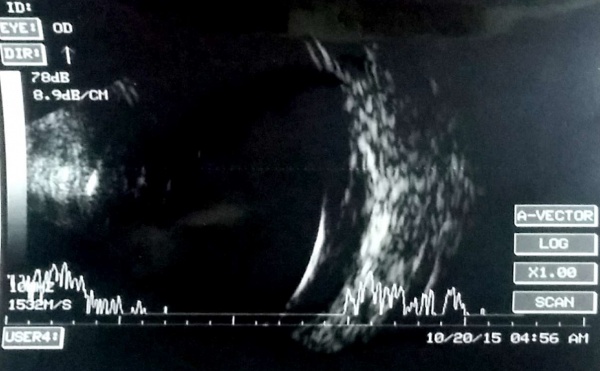

Dropped intraocular lens (IOL)

IOL is identified by high amplitude spike associated with acoustic reverberations.